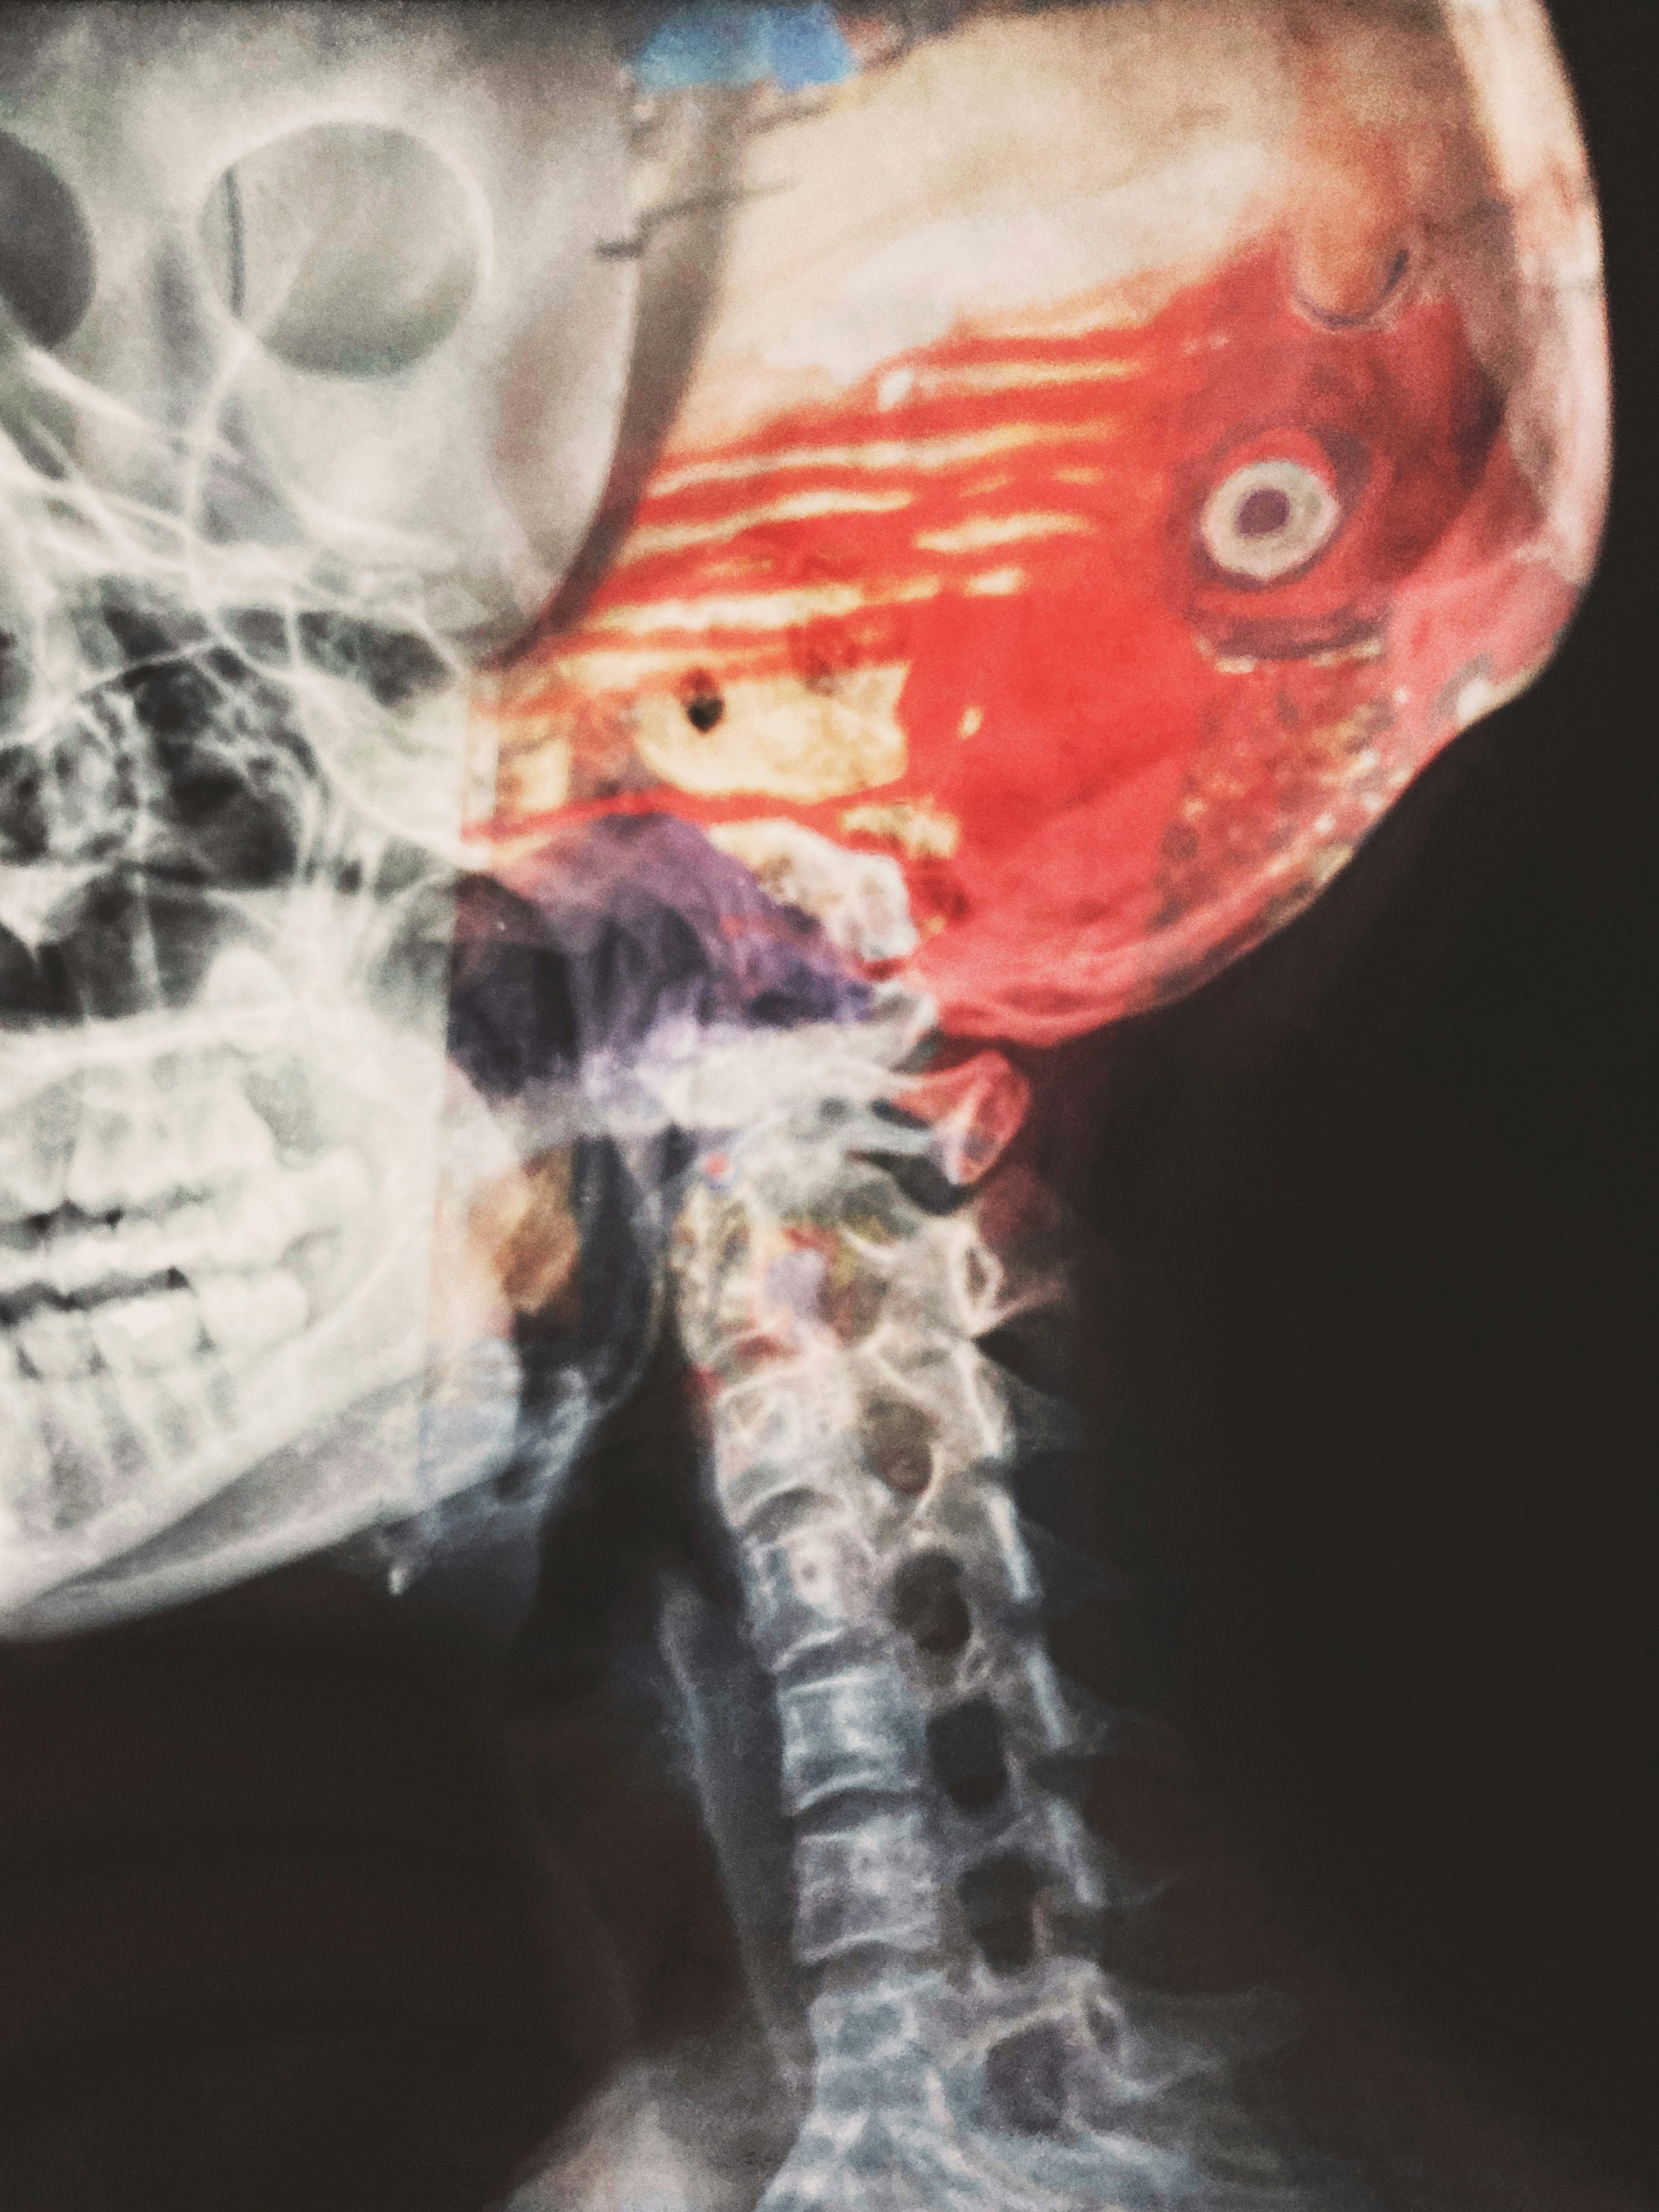

A. 두 질환의 초기증상은 매우 유사하여 증상만으로는 구별이 거의 불가능합니다. 다만 뇌출혈은 갑작스러운 극심한 두통, 구토, 의식 저하가 더 흔하고, 증상이 더 급격하게 악화되는 경향이 있습니다. 하지만 정확한 진단은 병원에서 CT나 MRI 검사를 통해서만 가능하므로, 증상이 나타나면 즉시 응급실로 가야 합니다.